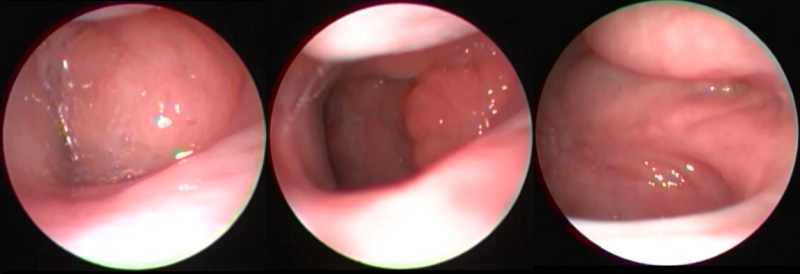

KBB - Kulak Burun BoğazGeniz Eti - AdenoidSağlık ve Hastalıklar Geniz Eti Ameliyatı Ne Zaman Olmalı? Yazar Op. Dr. Atilla Şengör Share Facebook Twitter Google+ Pinterest WhatsApp Geniz Eti Ameliyatı Ne Zaman Olmalı Büyümüş geniz etinin 2 yaşından itibaren hatta bazen acil durumlarda 2 yaş altında da alınması uygun olmaktadır.